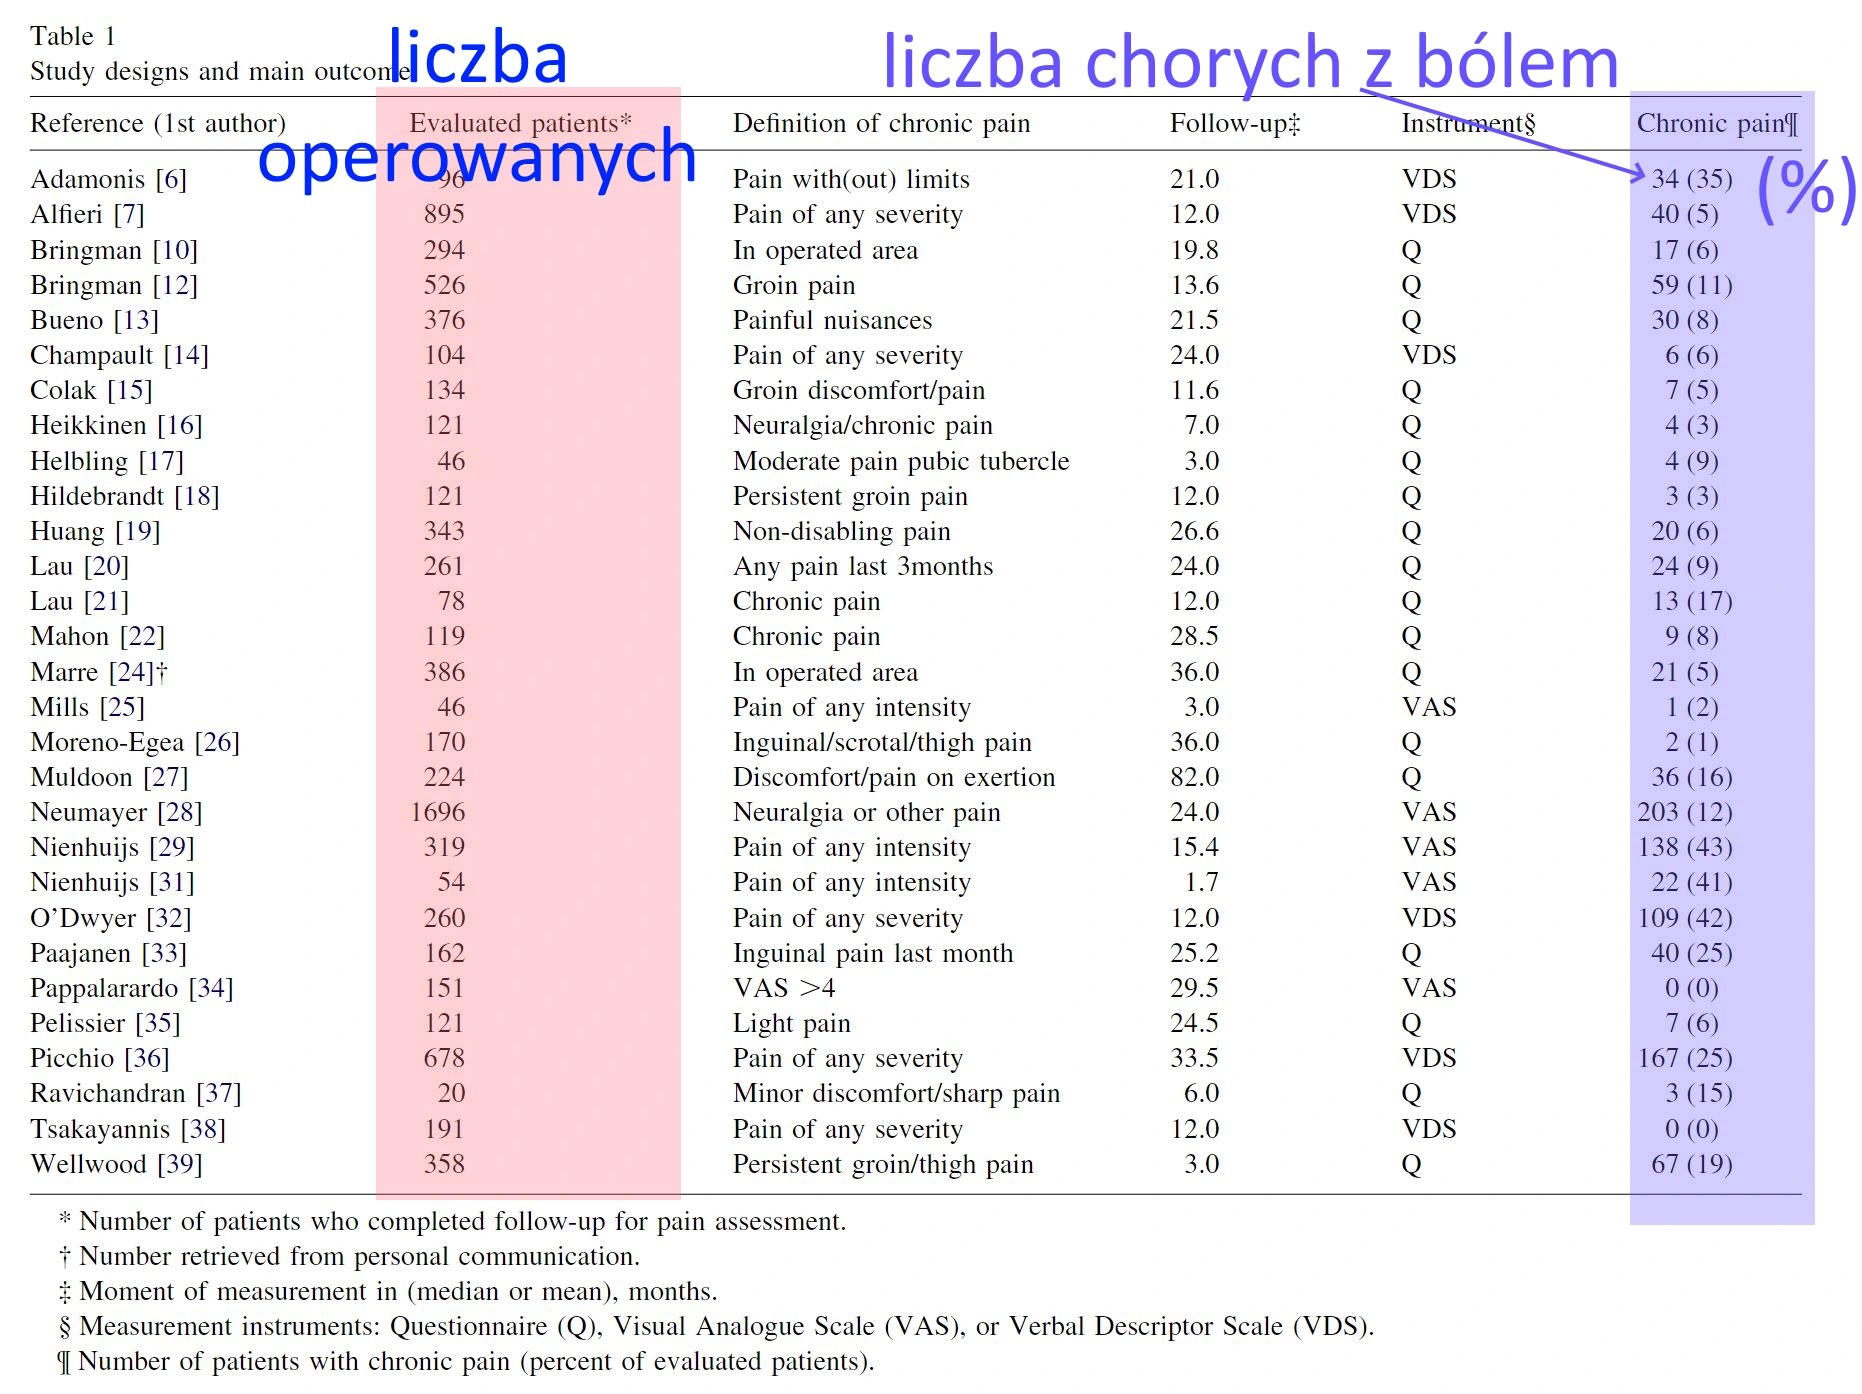

Ból po operacji przepukliny to poważny problem, dotykający co najmniej co 10. -20. operowaną osobę. Gdy ból po operacji nie ustępuje po 3 miesiącach - zwiastuje to poważny problem, gdyż jest to ból przewlekły, który sam nie ustąpi. Przyczyną bólu jest zwykle stałe drażnienie nerwu. Powstaje to w przypadku, gdy w czasie operacji uszkodzono osłonkę nerwu lub przyszyto nerw do siatki lub jest uwięziony w węźle szwu. W takim przypadku objawy nie ustępują a usuwa je jedynie operacja.

Jak często jest przewlekły ból (trwa ponad 3 miesiące od operacji) po operacji przepukliny pachwinowej? zobacz